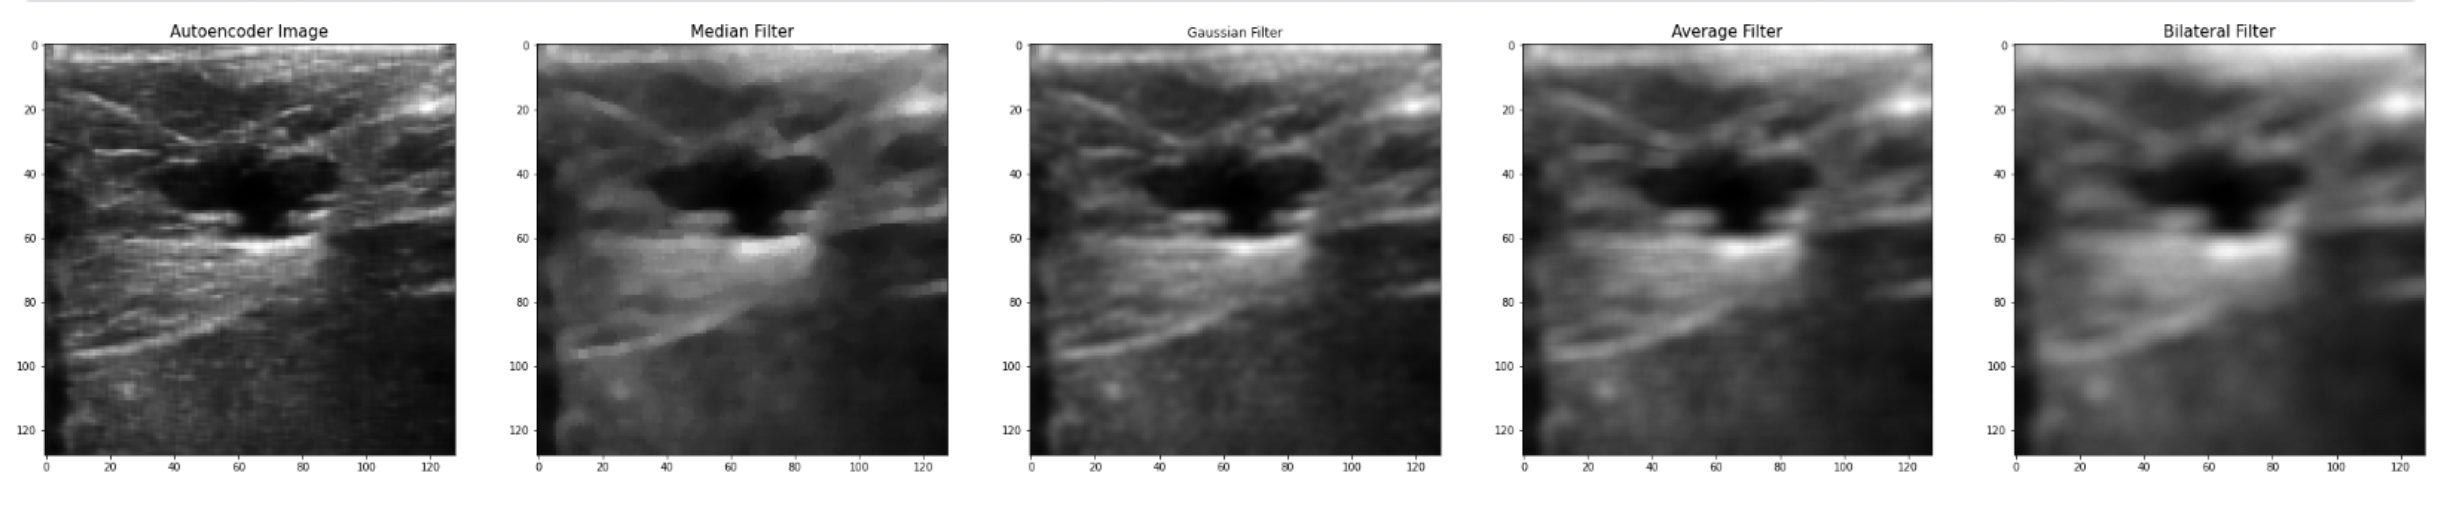

The best PSNR results we have reached so far, as mentioned earlier is (PSNR = 30.44), while at the Median filter, it was (PSNR = 25.362), Gaussian filter (PSNR = 27.541), Average filter (PSNR = 24.934), and Bilateral Filter (PSNR = 23.675), as shown in details at table II, and we can conclude from these results that the CNN Autoencoder is better that the other filtering techniques by 20.02%, 10.52%, 22.08%, and 28.57%, respectively. These results came at an epoch size of 30, batch size of 16, and 256 filters in each of the CNN Layers using the combined dataset which consists of 1568 breast ultrasound images. Below is the training vs validation loss graph , as well as the output image compared to old filtering techniques.

While the best MSE results we have reached so far, is (MSE = 0.0009), while at the Median filter, it was (MSE = 0.0022), Gaussian filter (MSE = 0.0017), Average filter (MSE = 0.0028), and Bilateral Filter (MSE = 0.0034) and we can conclude from these results that the CNN Autoencoder is better than the other filtering techniques. These results came at an epoch size of 50, batch size of 16, and 256 filters in each of the CNN Layers using the combined dataset which consists of 1280 breast ultrasound images, also the same MSE came at an epoch size of 30, batch size 16, and 256 filters in each of the CNN Layers, and a dataset of size 1568 ultrasound images.

The best SSIM results we have reached so far is (SSIM = 93.5%) while at Median filter it was (SSIM = 78.5%), Gaussian filter (SSIM = 87.1%), Average filter (SSIM = 76.9%), and Bilateral Filter (SSIM = 70.7%) and we can conclude from these results that the CNN Autoencoder is better than the other filtering techniques. These results came at an epoch size of 30, batch size of 16, and 256 filters in each of the CNN Layers using the combined dataset which consists of 1568 breast ultrasound images.